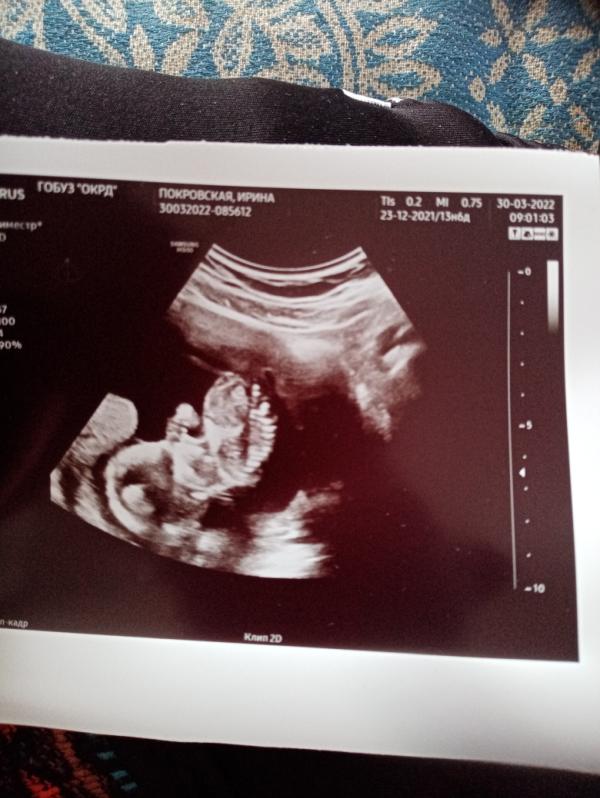

УЗИ в Великом Новгороде: 14 недель беременности, здоров, фото малыша! Отчет

Сегодня ездила на УЗИ в Великий Новгород. Сказали без двух дней 14 недель. Малыш здоров. 😅😘😏

Теперь хоть на человечка стал похож.

Зато есть теперь первое фото малыша ❤️